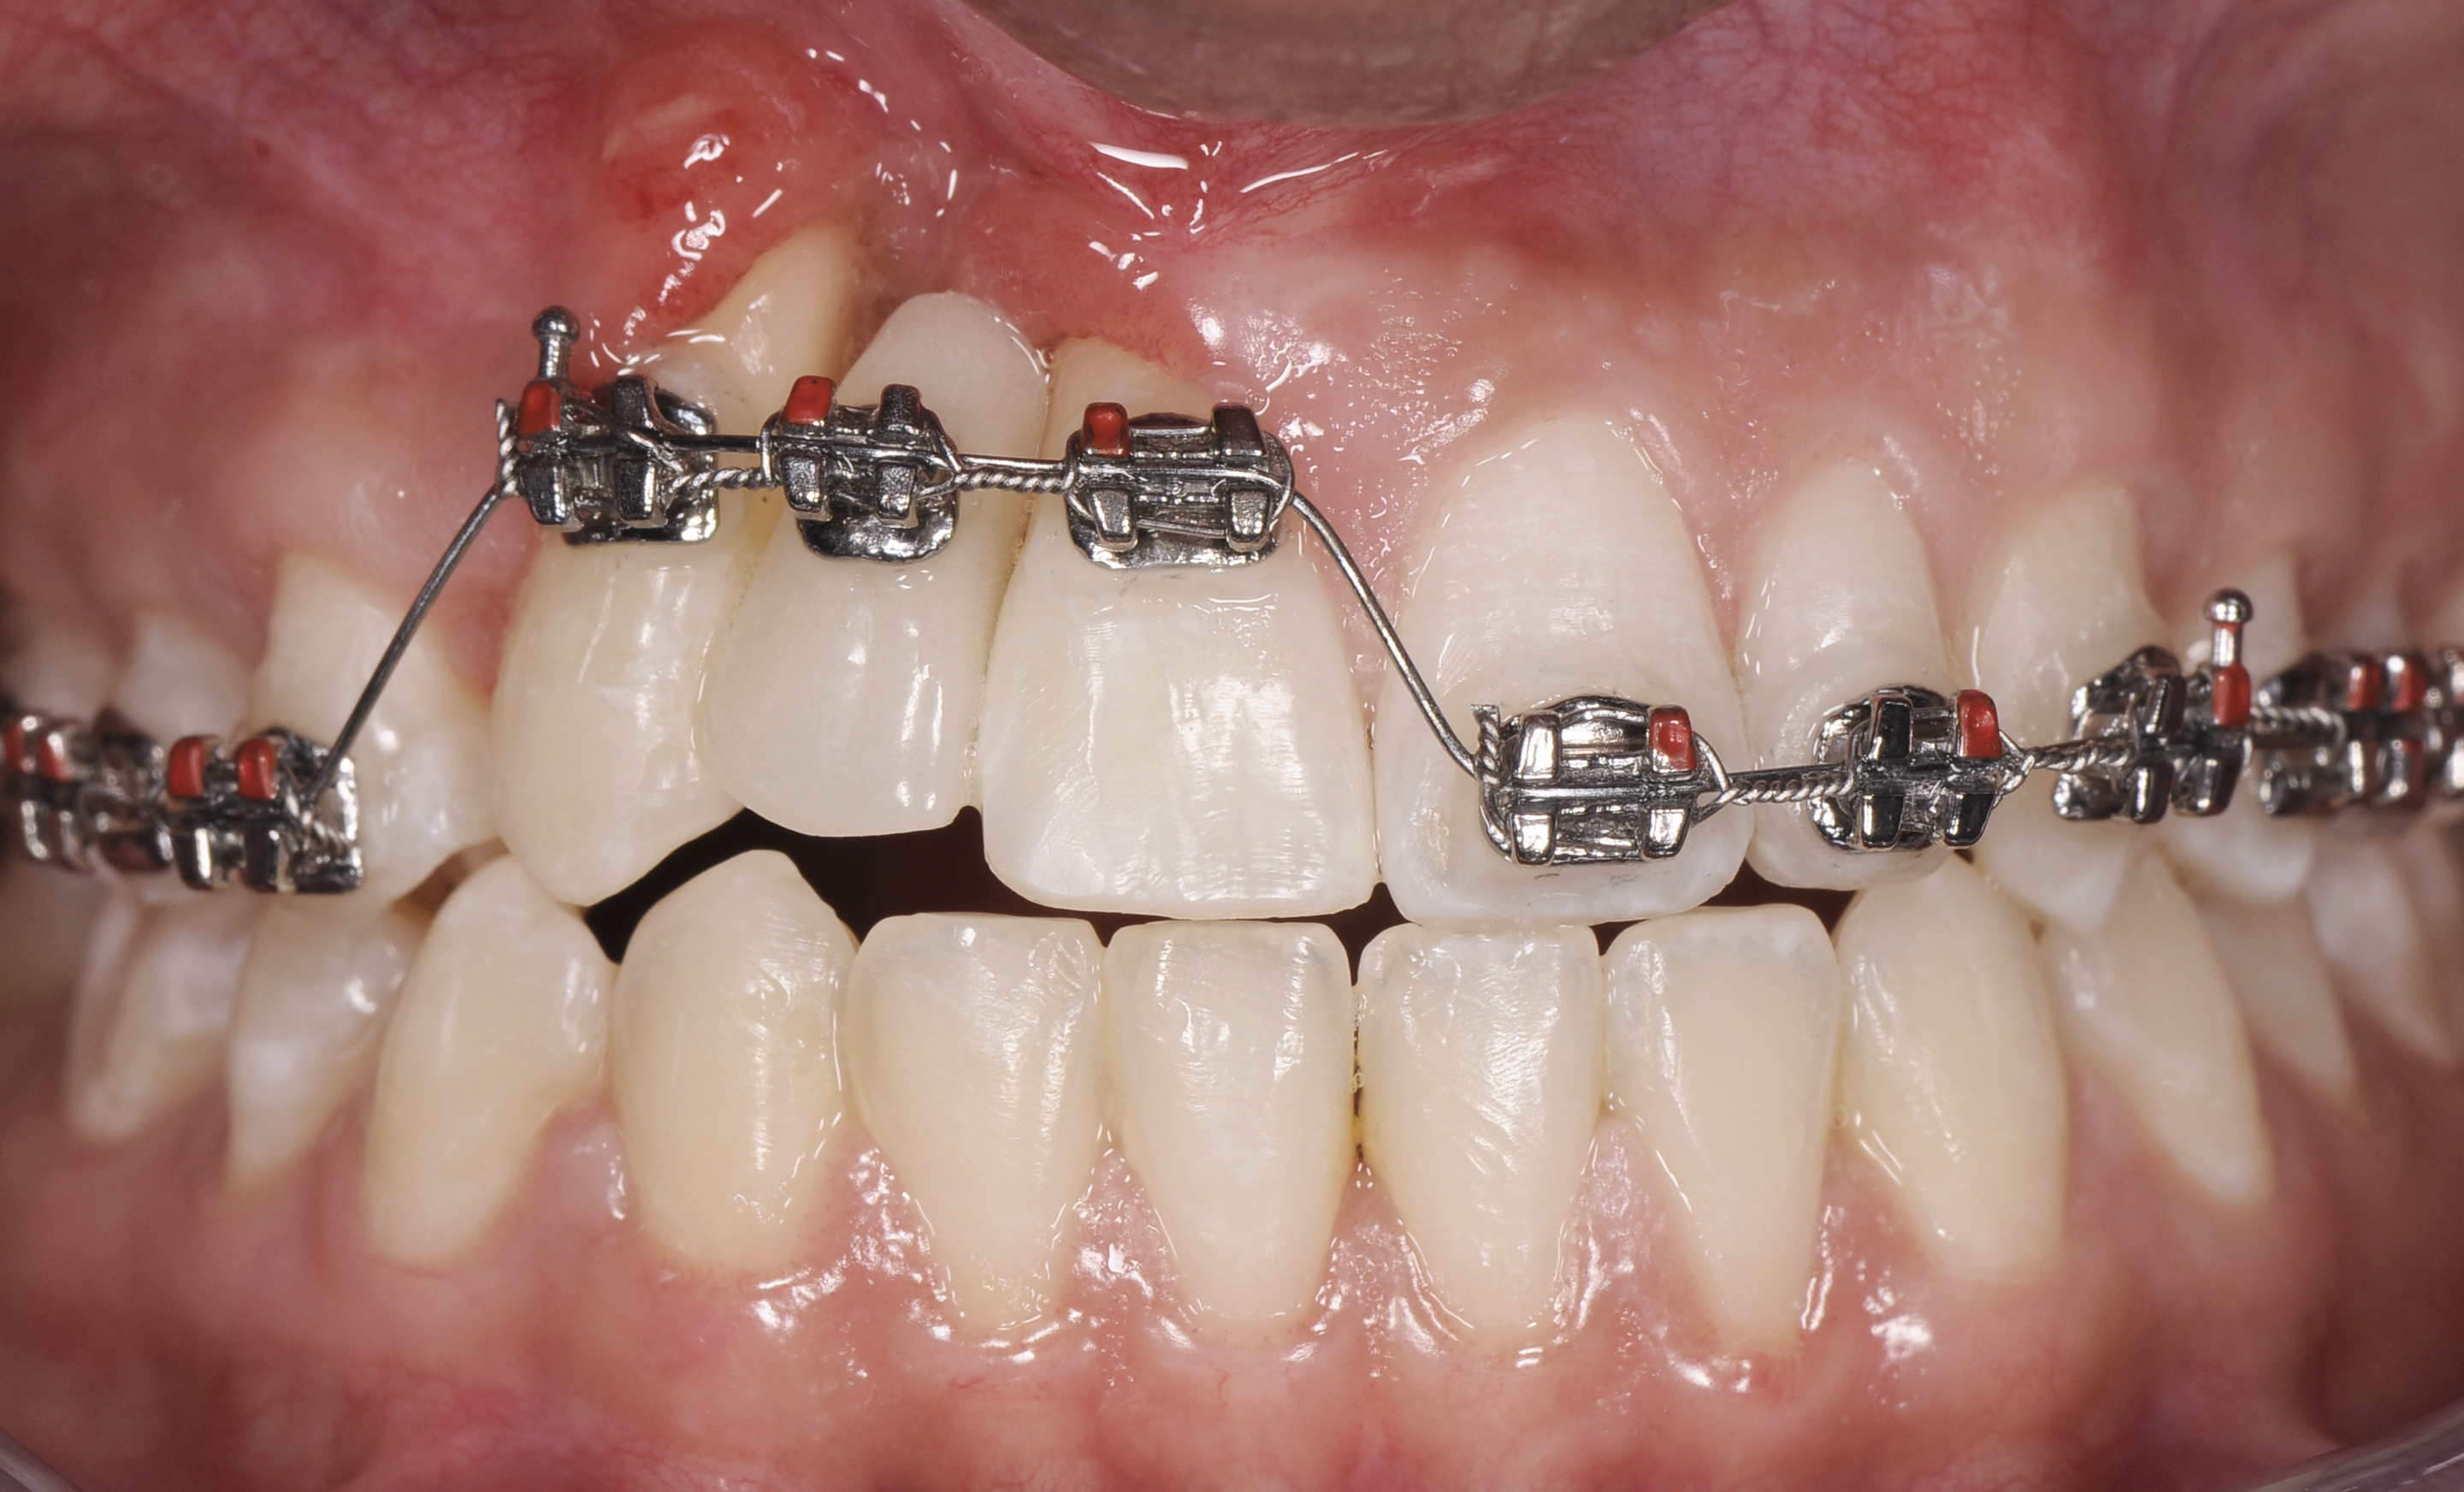

A healthy 20-year-old woman presented to the author’s office requesting treatment for a large defect in the area of missing tooth No. 7. She exhibited a high smile line that revealed a clearly visible deformity, associated with pain and sensitivity on teeth Nos. 6 and 8 and in the area of tooth No. 7 (Figure 1). Although the patient wore a modified Essix retainer, the defect was still visible because of the magnitude of tissue loss and the revealing nature of her smile.

Due to its predictability in achieving bone remodeling and developing alveolar ridge height while preserving or improving soft-tissue architecture, forced eruption was included as part of the interdisciplinary approach to treat the patient in the present case (Figure 5). Only stretching forces are applied to the periodontal ligament during the forced-eruption movement. This provides the stimulus for bone apposition within the socket walls. Generally, the orthodontic movement should be controlled so the root is extruded without impinging on the socket walls. In the presence of periodontal health, bone apposition and gingival remodeling will result in coronal proliferation of the attachment apparatus.29,30

Successful outcomes with forced eruption require the establishment of treatment endpoints, which may include overcompensation beyond the desired soft- and hard-tissue changes. For the present case, achieving ideal gingival-alveolar socket architecture required force-erupting tooth No. 6 to the level of the apical third and tooth No. 8 beyond the confines of its alveolus. As the gingival sulcus is everted through the eruption process, a gingival red patch corresponding to the nonkeratinized sulcular epithelium may appear, as shown around tooth No. 8 in Figure 8 and Figure 9. This tissue will develop into keratinized gingiva when exposed to the oral environment.31,32 Additionally, when forced eruption of this magnitude is performed, there may be a tendency for lingual displacement that needs to be addressed with root-torquing orthodontic auxiliaries (Figure 6 and Figure 7).